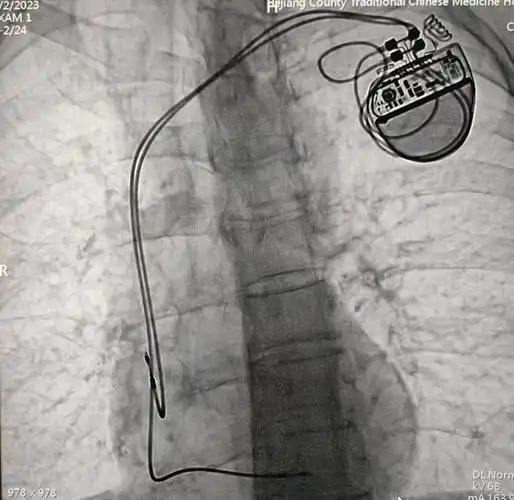

3例心脏人工永久双腔起搏器植入术成功开展